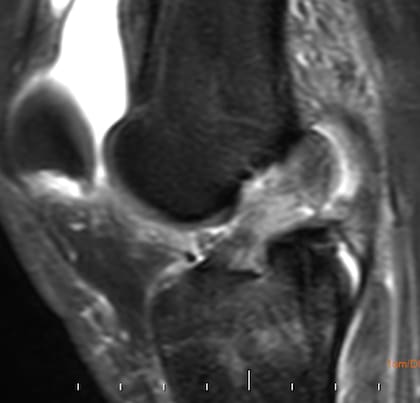

Si bien el diagnóstico puede realizarse con el examen físico (las maniobras semiológicas mencionadas). Los métodos por imágenes son imprescindibles para su confirmación y evaluación del resto de las estructuras (meniscos, hueso). Es importante realizarlos en un lugar confiable y donde los médicos radiólogos tengan comunicación con los traumatólogos. La resonancia magnética es el estudio de elección.

Para una mejor visualización, la resonancia magnética debe realizarse en un equipo de alto campo (1.5 tesla o 3 tesla) que permiten ver lesiones óseas en meniscos u otros ligamentos en profundidad. En cambio, la tomografía computada, sirve para visualizar lesiones asociadas del hueso, con una limitada visualización de partes blandas. En tanto, con una ecografía no se logra visualizar los ligamentos cruzados, ya que son estructuras profundas.